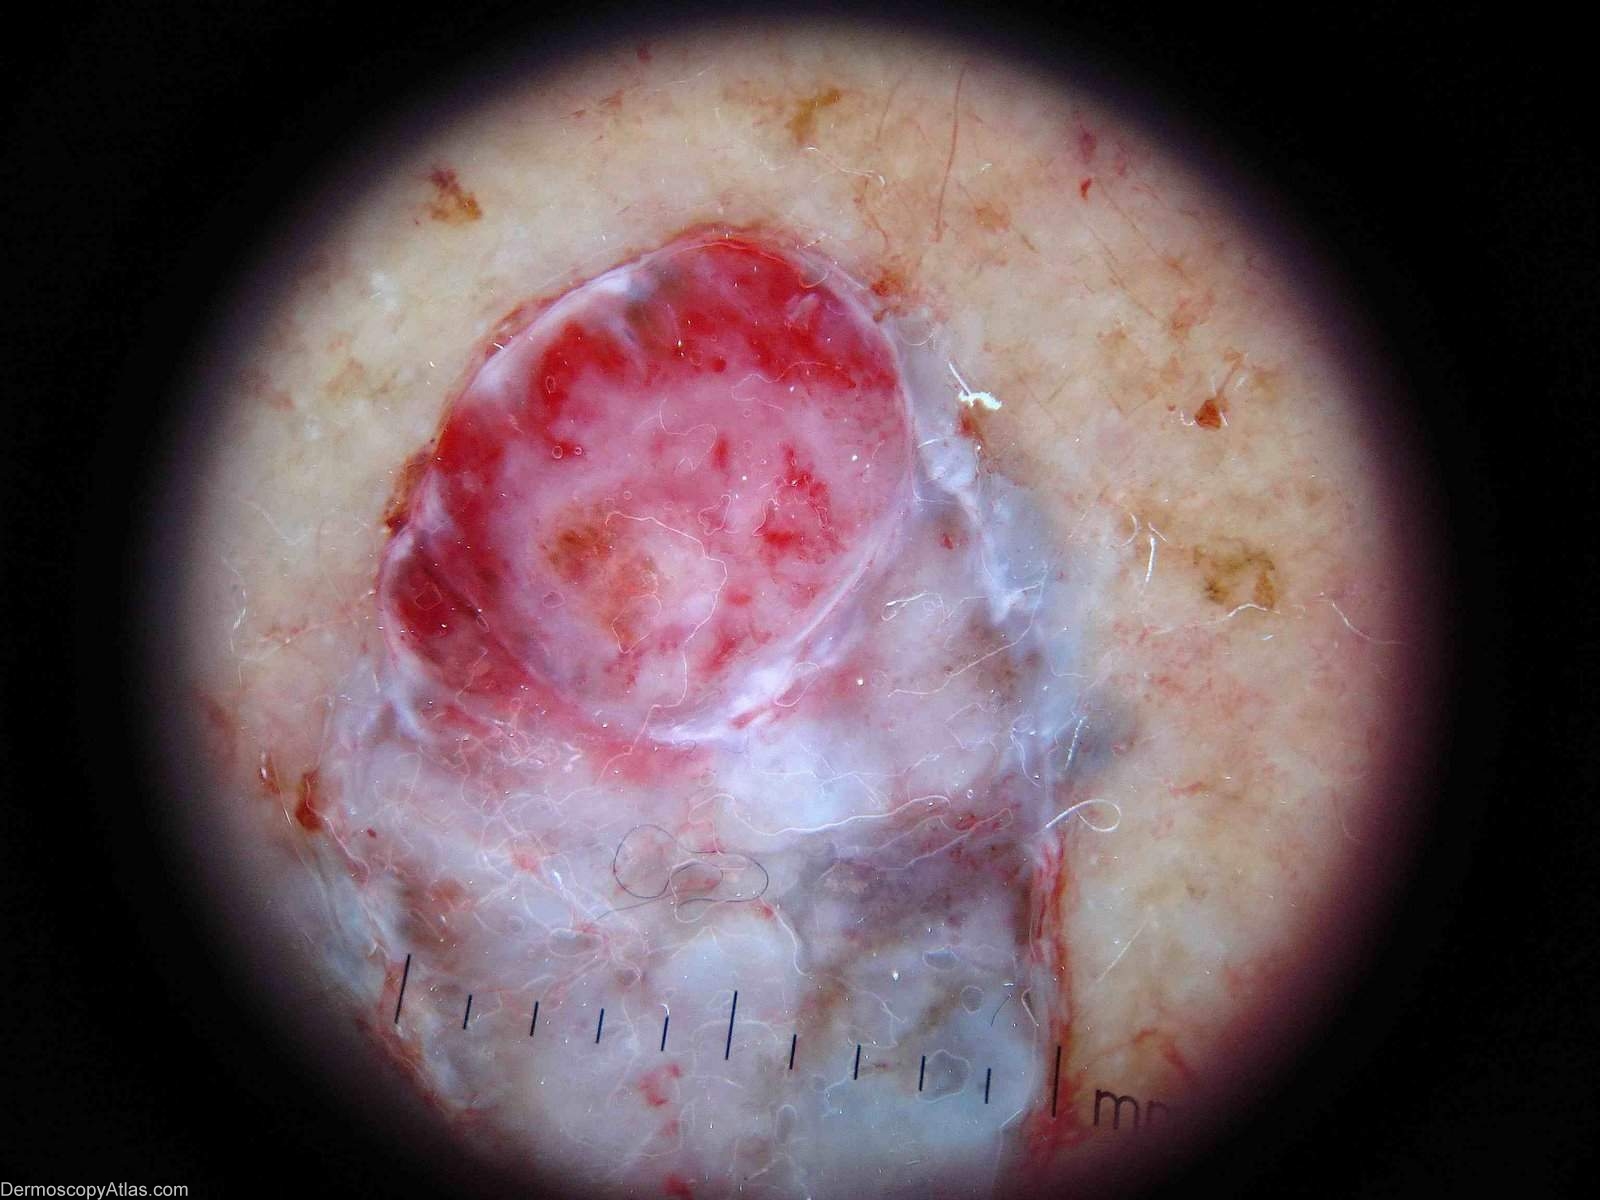

Image Number #2386 (Pigmented basal cell carcinoma)

Site: Leg

Diagnosis: Pigmented basal cell carcinoma

Description: Dermatoscopy of blue nodule on leg. There are massive blue ovoid nests without a network.

Sometimes pigmented BCCs can look so blue they resemble melanomas. The other two images are courtesy of Dr Martin Baker illustrating the came point. These two are even more suggestive of malignant melanoma.